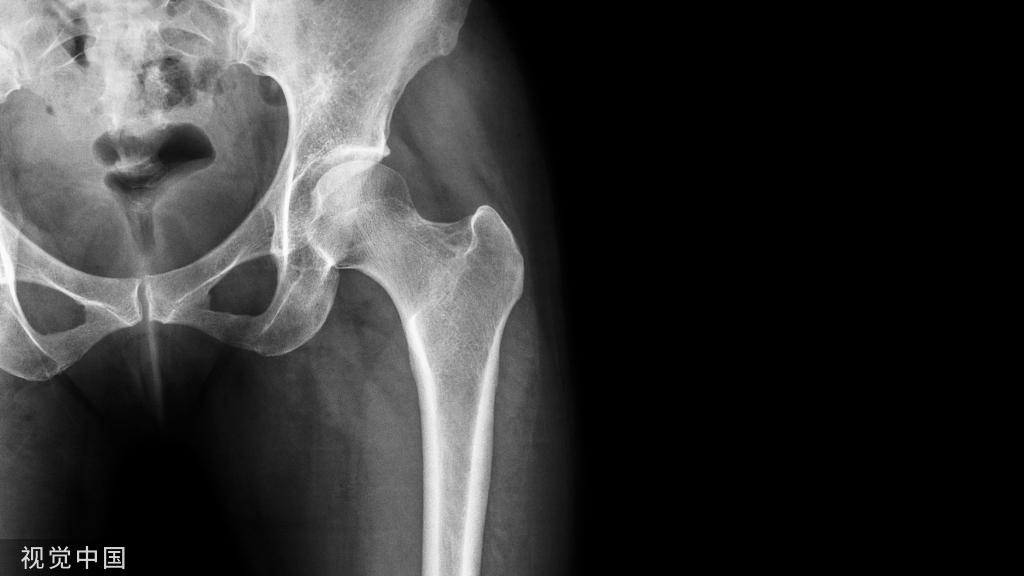

股骨远端骨折或干骺端骨折占所有骨折的1%,占所有股骨骨折的4-6%。在这些病例中,髓内钉用于股骨远端骨折时,出现复位困难和相对较高的骨折移位率、畸形愈合、延迟愈合和不愈合等情况。发生这种现象通常与股骨远端干骺端区域的宽度有关。

在这些病例中逆行髓内钉(RIMN)避免这些问题。逆行髓内钉可获得较长的工作长度,允许多枚远端螺钉插入,因此具有更稳定的结构。尽管具有这些优势,但RIMN仍会导致进针点关节软骨损伤,膝前痛仍是最常见的术后并发症之一。